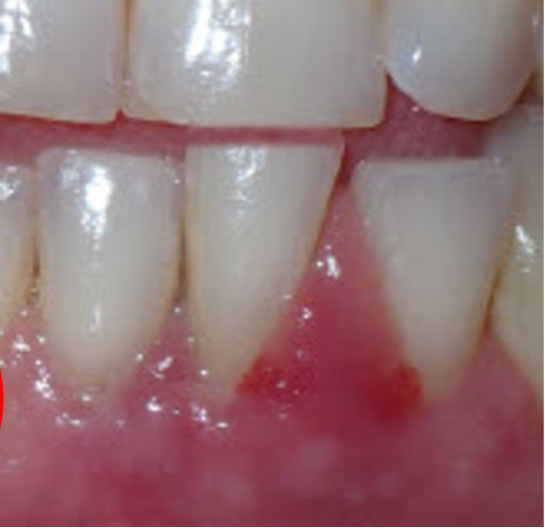

The tissue had already settled down.

My son, Dr. Matt Sheldon, splinted tooth #24 (to #23 and #25), but she was feeling better even before the splint was placed. Infection control—not extraction—was already changing the outcome.

Weeks later, pocket depths had dramatically improved—nearly all were resolved.